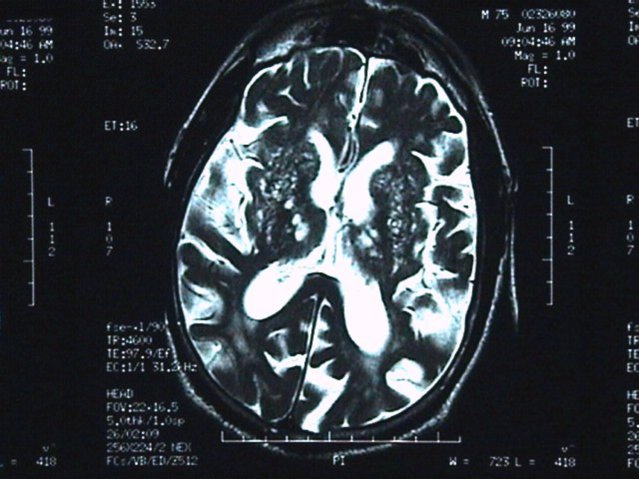

I punti bianchi, medi e piccoli, rappresentano innumerevoli ictus che causano la demenza vascolare (Fonte: Budson & Solomon, 2016)

Sebbene individui e membri della famiglia notino di solito gli ictus più importanti provocati dal blocco delle grandi arterie, i piccoli ictus derivanti dal blocco delle piccole e microscopiche arterie nel cervello sono in genere silenziosi. Per vedere questi ictus nei piccoli capillari è necessario uno studio di scansione del cervello con risonanza magnetica o TAC.

Alcune persone hanno molti più di questi piccoli ictus o possono avere un numero di ictus medi o grandi. Quando gli ictus sono la causa principale dei problemi di pensiero e di memoria, usiamo il termine 'demenza vascolare' se il funzionamento quotidiano è compromesso e 'deterioramento cognitivo vascolare' se la funzionalità quotidiana è normale.